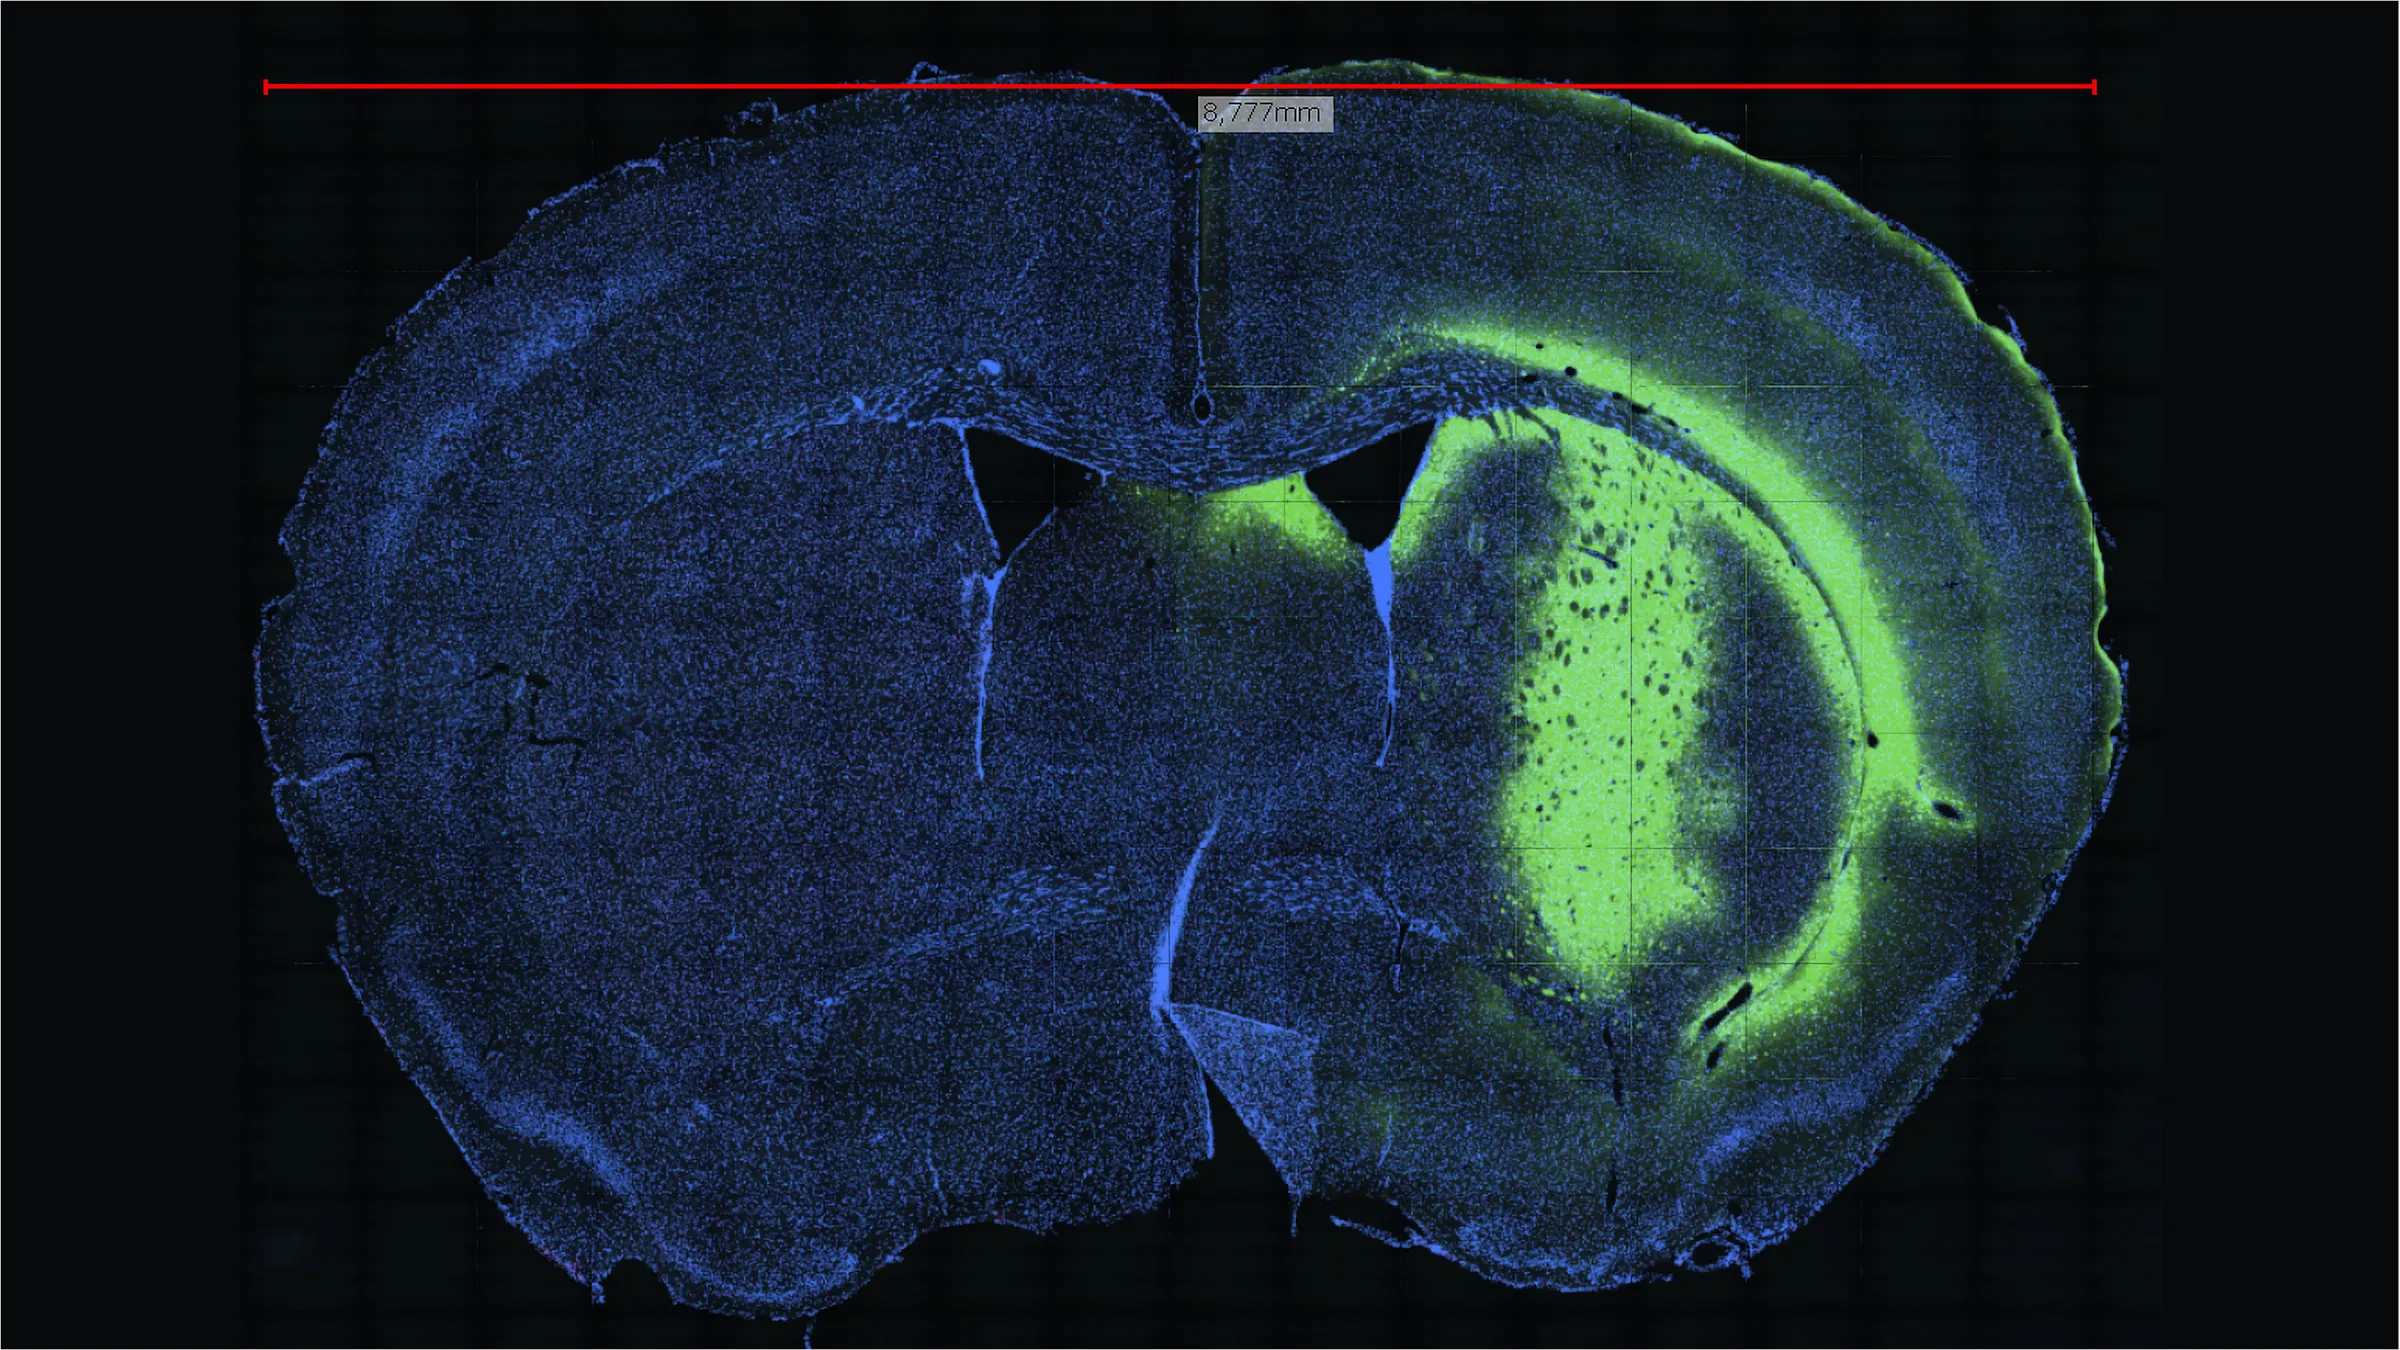

Cross-section of a brain in millimeter scale

Cross-section of a brain in millimeter scale: in a biopsy or autopsy, extracted tissue is prepared before the investigation in extremely thin cross-sections or brought into a solution and, if necessary, stained for better depiction of specific features.

Image-based cytometry using NYONE allows us to have a deep insight into the processes of life. With resolutions from millimeters to the nanometer scale, NYONE gives us a better understanding of the metabolic processes in cells.